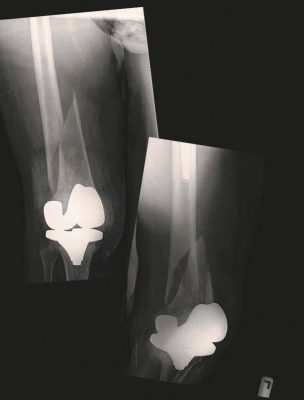

У братьев Янг есть такие возможности, и всё же они четыре года боролись за то, чтобы выяснить, как у их матери, которая не могла передвигаться самостоятельно, случилось два одинаковых перелома каждой бедренной кости, когда она жила в доме для престарелых Chartwell Waterford Long-Term Care Residence. Никто тогда не сообщил им о травме.

Хирург-ортопед и радиолог, изучившие рентгеновские снимки Джудит, пришли к заключению, что переломы не стали следствием хрупкости костей. Они были вызваны «значительной силой вращения».